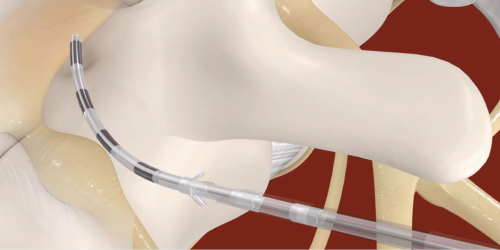

Metoda neuromodulacji polegająca na elektrycznej stymulacji nerwów obwodowych za pomocą elektrod umieszczonych w pobliżu docelowego nerwu. Celem terapii jest modulacja przewodzenia bodźców bólowych i redukcja przewlekłego bólu, szczególnie o charakterze neuropatycznym.

Nasze systemy neurostymulacyjne wyróżniają się unikalną, bezprzewodową konstrukcją, w której elektroda i stymulator stanowią jedno urządzenie. Takie podejście umożliwia jednoczasową implantację, bez konieczności wykonywania drugiego zabiegu oraz bez implantacji baterii w ciele pacjenta.

brak implantowanej baterii

brak kabli łączących pod skórą

zewnętrzne, ładowalne źródło zasilania

brak nagrzewania (nie indukcja)

elastyczne pozycjonowanie baterii (20–50 cm)